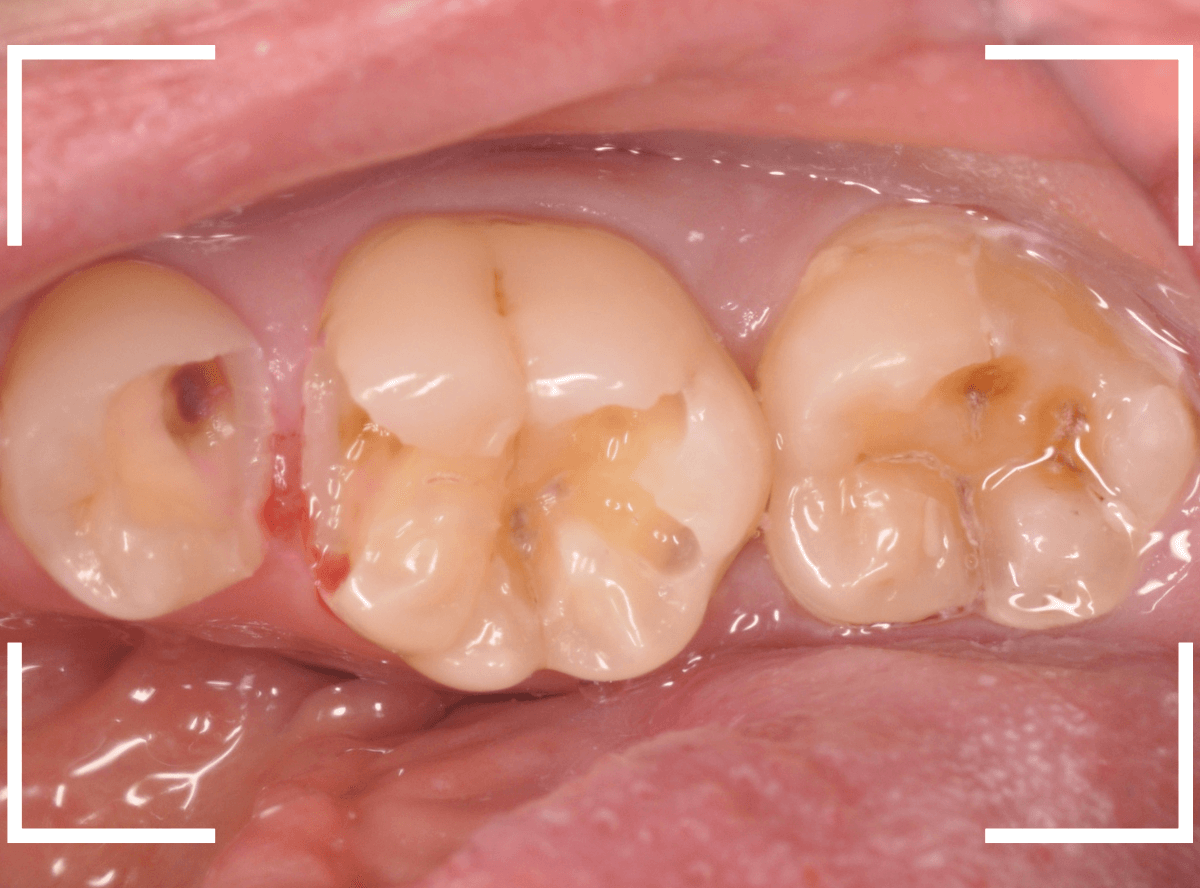

虫歯の治療を開始します。

隣の歯とのすき間を中心に広い虫歯になっていました。

虫歯治療後、特に症状もなく経過観察できましたので、つめものを作る治療に入ります。

セラミック治療をご希望されましたので、

小臼歯をE-MAX・インレー、

大臼歯をジルコニア・インレーで処置することになりました。